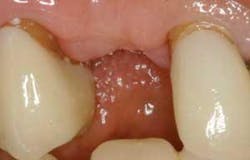

Figure 1 - Preop facial view. Adequate soft tissue was present to provide papilla formation, provided the implant crown emergence profile was properly formed.